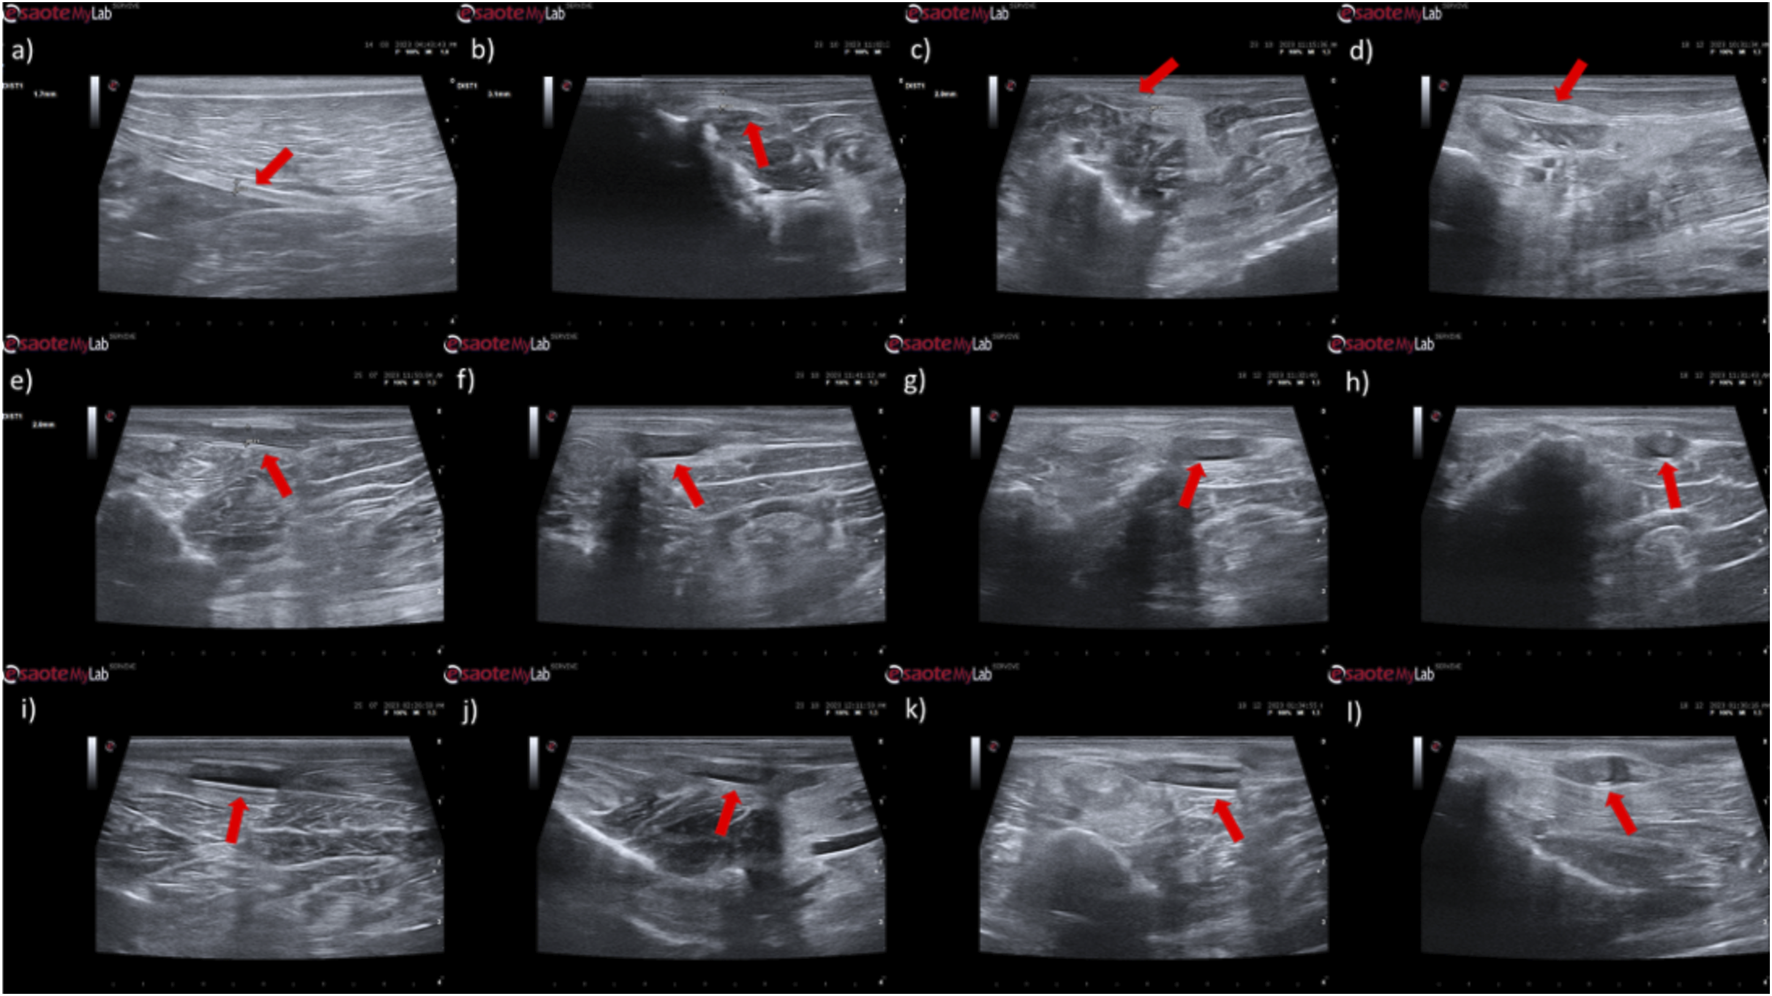

The results of the ultrasound evaluation of the common peroneal nerves can be seen in the Figure 7 and Figure 8 for the ultrasound images obtained and for the results of nerve diameter measurements, respectively. The complete values of nerve diameter measured using ultrasound can be found in Supplementary Table S10, and the statistical differences observed in T24 in Supplementary Table S11.

FIGURE 7

Ultrasonographic appearance of the common peroneal nerves submitted to different treatments. (a) intact common peroneal nerve (UC); (b–d) nerves that received an EtE suture 1 month, 3 months and 6 months after injury, respectively; (e–g) nerves that received a NGC 1 month, 3 months and 6 months respectively; (h) nerve that received a NGC 6 months after surgery, transversal section; (i–k) nerves that received the combination NGC-CM 1 month, 3 months and 6 months after injury, respectively; (l) nerve that received the combination NGC-CM 6 months after surgery, transversal section. In each panel, the red arrow indicates the common peroneal nerve or common peroneal nerve + NGC set.

In animals that received EtE sutures, after 1 month (Figure 7b) an increase in nerve diameter associated with typical swelling due to edema and inflammation observed in the initial phases of the regenerative process was observed. The nerve appears hypoechoic and has a disorganized architecture, where the fascicular pattern of the healthy nerve (Figure 7a) is lost, particularly distal to the lesion and suture site. Hypoechoic areas derived from post-surgical effusion are also observed around the nerve. After 3 months (Figure 7c) the diameter of the nerve increased further, and a hypoechoic appearance with structural disorganization of the nerve continues to be observed, particularly distal to the site of injury and suture. Despite this, perinervous edema appears to have decreased, although some hyperechogenicity associated with the formation of perinervous scar tissue is observed. At 6 months (Figure 7d) the diameter of the nerve remains identical to the previous timepoint, but with evident ultrasound improvements. The hypoechogenicity associated with edema and local inflammation disappears, and a fascicular organization close to normality is observed along the nerve, with the site of injury and suture not being easily distinguished. Some hyperechogenicity associated with scar tissue is still observed, but to a lesser extent compared to the previous timepoint.

In the groups that received NGCs, the tubes are observed as hyperechoic tubular structures, well differented from neighboring tissues, and it is possible to observe the nerve tops introduced inside their lumen. After 1 month (Figures 7e,i) mild hypogeneity was observed around the NGCs (particularly in the NGC-CM group) derived from edema resulting from surgical manipulation. Nerves are observed only at the ends of the NGC, and the lumen of the NGC appears hypoechoic due to the content of inflammatory exudate associated with the normal process of axonal regeneration and regrowth. After 3 months (Figures 7f,j) signs of early continuity are already observed, with a band of nervous tissue occupying the entire length of the NGC, reflecting the continuity of early tissue across the gap. This nervous tissue, however, still appears hypoechoic and without the typical fascicular organization. As the nerves do not occupy the entire internal diameter of the NGC, hypoechoic areas are observed, probably occupied by edematous and inflammatory content. Hypoechogenicity at the periphery of the NGC decreases, being replaced by hyperechogenicity associated with the formation of fibers and scar tissue derived from surgical manipulation and the presence of the NGC. After 6 months (Figures 7g,k) the NGCs are still visible, revealing little or no degradation of the material over the 6 months of implantation. At this timepoint, consolidated nervous continuity is already observed along the entire length of the NGC, with a significant decrease in hypoechogenicity and with the observation of a fascicular organization close to normality. The nerve diameter in the NGC-CM group decreased markedly, not occupying the entire NGC lumen and leaving hypoechoic empty spaces around it. The nerve diameter in the NGC group remains larger. The hyperechogenicity associated with the accumulation of fibrous and cicatricial tissue around the NGCs remains. These features are also visible in a cross section (Figures 7h,l).

When determining the ultrasonographic diameter, an increase in the nerve diameter was observed 1 month and 3 months after the surgical injury and application of therapeutic options. After 6 months, there was a decrease in the diameter of the common peroneal nerves in all groups, more markedly in the EtE and NGC-CM groups, with NGC being the one with the largest final diameter. After 1 month, statistically significant differences were observed only between UC and EtE (p = 0.0119), but with the increase in diameter in all groups, after 3 months differences were observed between the control group and all therapeutic groups (p < 0.0001 with EtE, p = 0.0049 with NGC and p = 0.0015 with NGC-CM, respectively). At 6 months, statistical differences remained with the UC group (p = 0.0178 with EtE, p = 0.0008 with NGC and p = 0.0168 with NGC-CM, respectively). Throughout the study period, no statistical differences were observed between the therapeutic groups under study, and at T24 the smallest diameter was observed in the EtE group, followed by NGC-CM and NGC, although in all groups with larger diameters than those of the non-intervened healthy nerves.